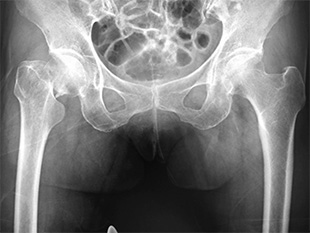

大腿骨近位部骨折(あしの付け根の骨折)

疾患と症状

高齢者の転倒で生じる骨折の中でも頻度が高い骨折です。

寝たきりの原因としての頻度が高く、早期の手術とリハビリが望ましいものです。

必要に応じて地域の他病院と連携しながら、もとの日常生活への復帰を目指します。

• 画像:大腿骨近位部骨折

(術前)